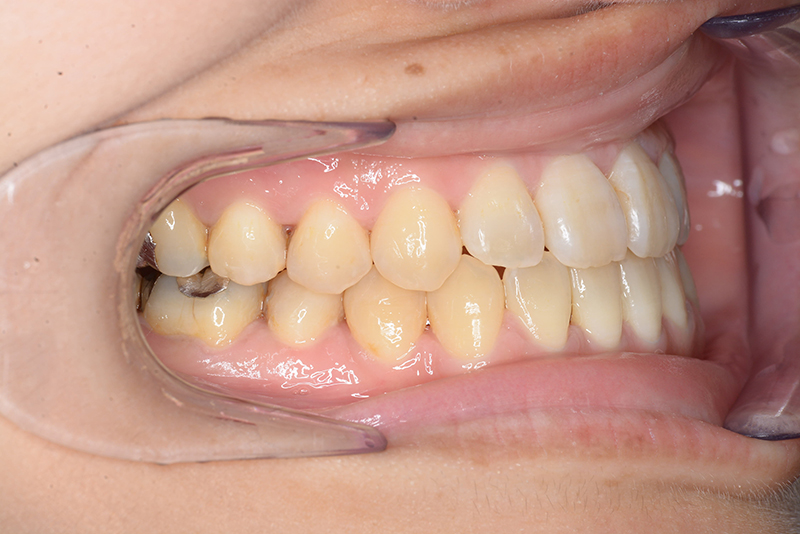

動的治療終了時

FP・IOP

批評・予后 ロウアングルのSkeletal Ⅲ級であり、下顎臼歯は近心傾斜しつつ7遠心部にはアップライトができるスペースがあると判断して、MEAWによる咬合平面の平坦化および可及的な下顎のカウンタークロックワイズローテーションによって改善を行うこととした。治療後には歯列の整直とⅠ級の咬合が得られた。(H30年9月現在で)保定開始4年経過しているが現在も咬合は安定している。